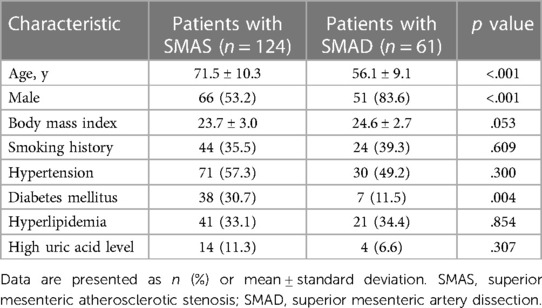

CT angiography (CTA) was performed on a 64-detector row scanner (Philips Core128, Rotterdam, The Netherlands). The scanning parameters were as follows: 120 kV; 312 mA; field of view, 362 × 362 cm; matrix, 512 × 512; and slice thickness, 0.5 mm. The locations of the plaque and dissection origins were assessed on the volume viewer using multiplanar reformatting and maximum intensity projections. The aortomesenteric angle was defined as the angle between the abdominal aorta major axis and the SMA ostium major axis (Figure 1A). The aortomesenteric angle and SMA-related distances were measured based on CTA findings (Figure 1B). All images were analyzed separately by 2 independent radiologists, both with >10 years' experience in vascular radiology. The measurements were repeated 20 days later, and the mean of the 2 sets of values was used for analysis.

Figure 1. Measurements obtained using findings from computed tomography angiography. (A) Measurement of the aortomesenteric angle (red lines) and location of the superior mesenteric atherosclerotic plaque (white arrow). (B) Measurement of the distance (red d) from the root of the superior mesenteric artery to the origin of the superior mesenteric artery dissection (white arrow).